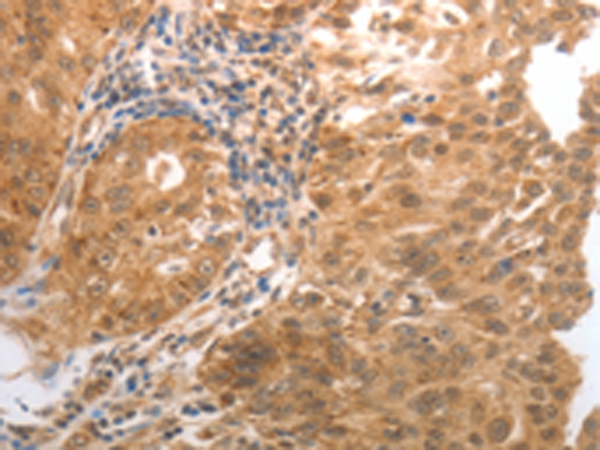

分类: 科研抗体货号: P11031别名: HNC, CLG1, MMP-8, PMNL-CL应用: WB,IHC反应种属: Human